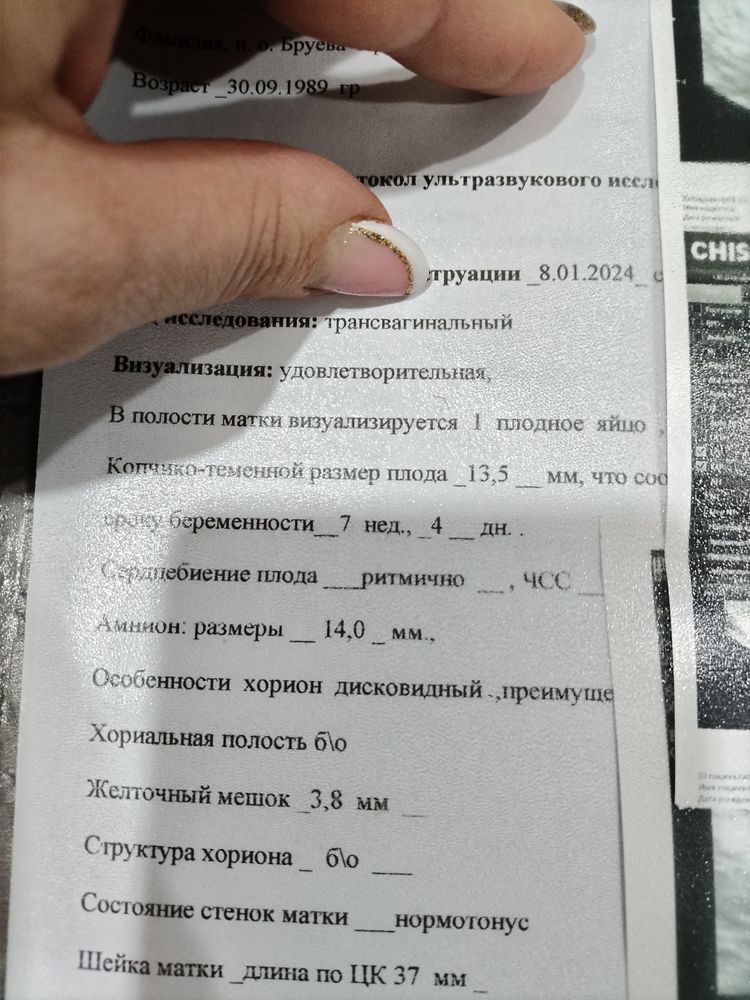

Добрый вечер. У меня срок 7,5 недель беременности от зачатия. Лечусь у гематолога: Клексан 0,4, ангиовит, дипиридамол, магний б6. На этом фоне забеременела, 14 лет беременности не было видимо была несовместимость с бывшим мужем, гематологу сдала разные анализы на мутацию, сказал что какие то гены сломаны, что именно сказать не могу. Сейчас с другим партнёром забеременела на второй цикл, на 4 неделе увидела однократное розовые выделения и забрали в больницу, проверили и была гематома, прокололи магнезию, Дротаверин, этамзилат. Сейчас сделала узи, срок 7,5 недель, было слабое сердцебиение 103, и тонкий хорион 2,3. Пью Актовегин. Через неделю после начала актовегина опять была на узи : сердцебиение 155, толщина хориона 5. Но начались редкие выделения светло розовые, врач узи говорит что эти выделения идут на фоне того что ворсинки хориона куда то имплантируются и еще колю Клексан и. Такая мазня может быть всю беременность. Сегодня такие выделения весь день. Симптомы токсикоза сохраняются. Сейчас принимаю дипиридамол, ангиовит, магний б6, праджисан, Клексан, калий йодид. По какой причине эти выделения и надо ли паниковать и бежать в больницу. Узи получится сделать только 11 марта. Кто сталкивался подскажите